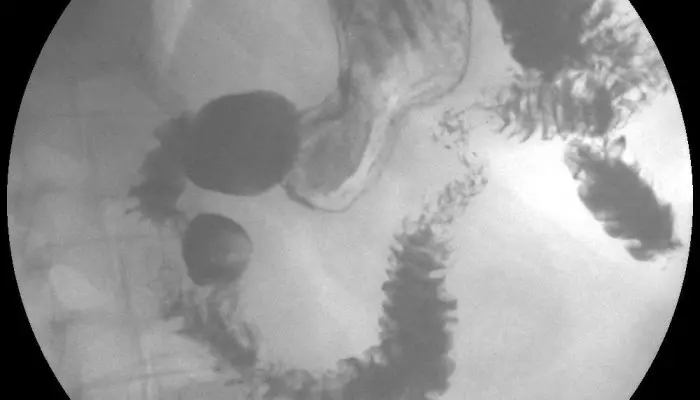

После того, как человек поест, орган становится объемным и приобретает форму, напоминающую полумесяц. Каскадный же желудок в наполненном состоянии больше напоминает крючок. На снимке, сделанном с использованием контрастного вещества, деформация желудка выглядит так:

- орган перегибается вокруг своей оси;

- верхняя часть похожа на чашу;

- нижняя – на трубку.

Снимки выполняются в нескольких проекциях с изменением положения пациента. На передней проекции можно увидеть, что деформированный желудок опущен ниже обычного.